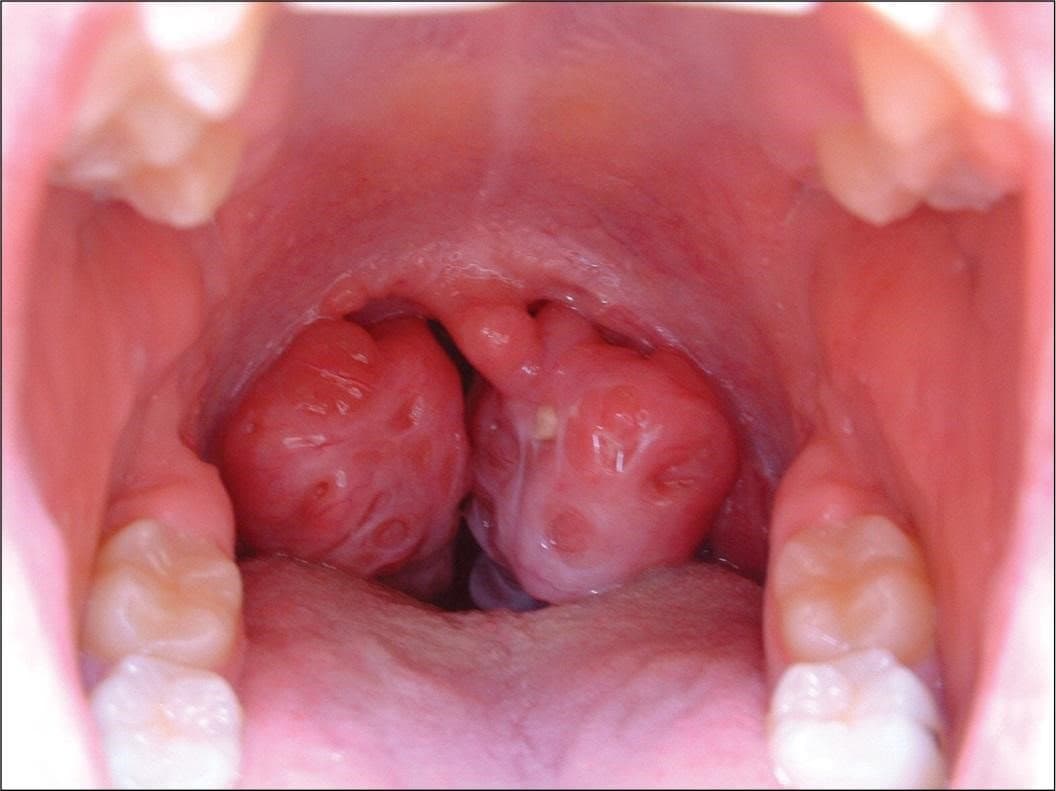

Hình ảnh viêm Amidan phát triển to, trở thành ổ bệnh chứa nhiều vi khuẩn gây hại cho cơ thể

– Khi há miệng quan sát sẽ thấy niêm mạc họng sưng đỏ, khi quan sát sẽ thấy khối Amidan sưng to.

– Khe rãnh Amidan có nổi mủ, đôi khi có những ổ áp xe xung quanh khu vực Amidan.